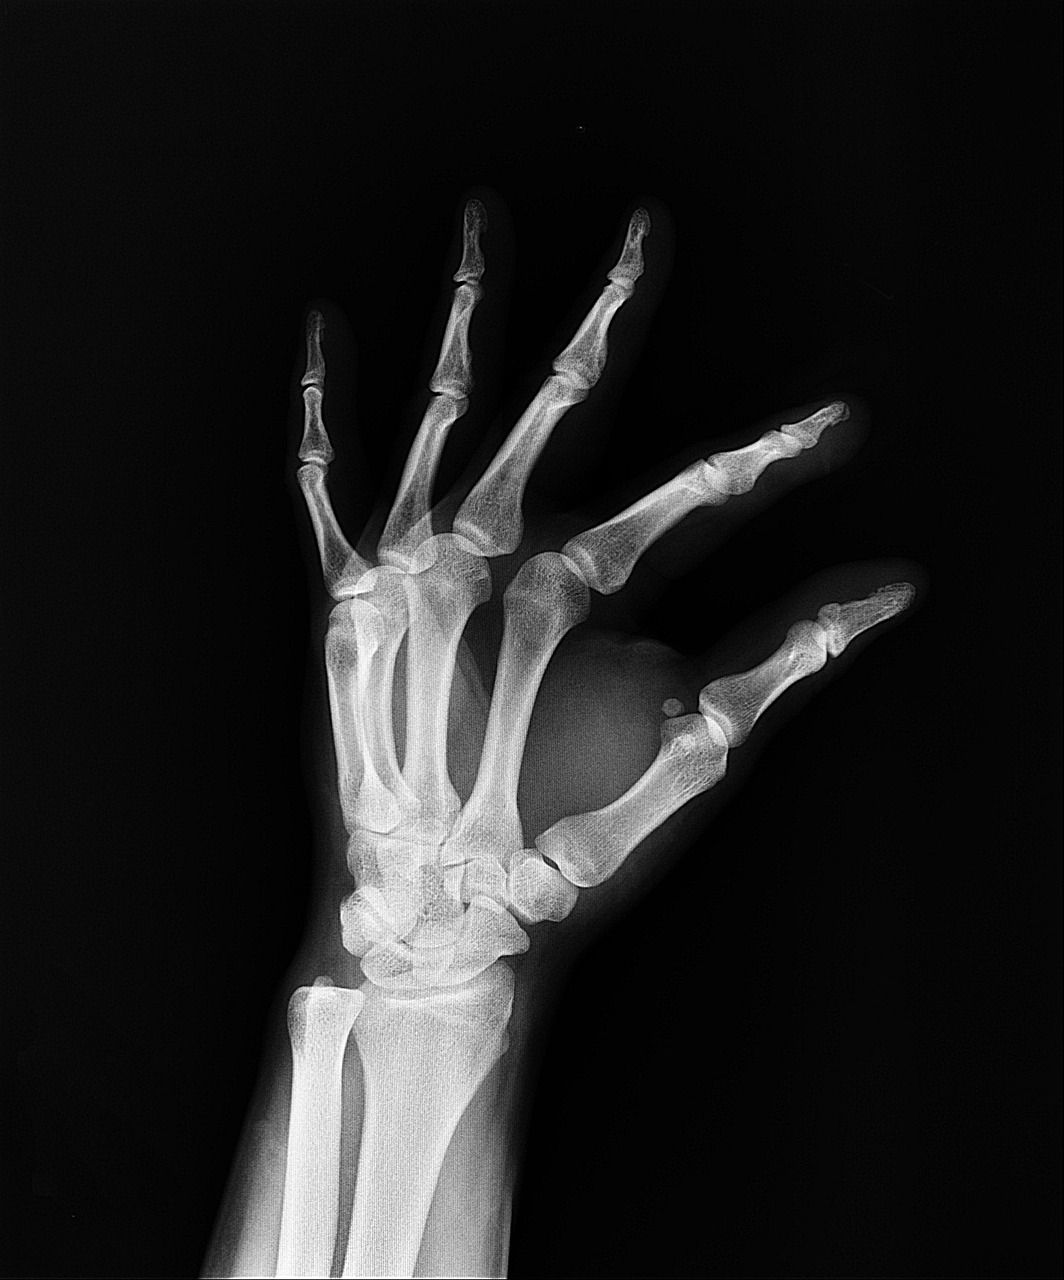

노인장기요양 등급 신청방법은 65세 이상이거나 65세 미만이라도 노인성 질환(치매, 파킨슨병 등)이 있는 경우 신청이 가능합니다. 저희 가족도 처음엔 고령이라 자동으로 혜택이 주어지는 줄 알았는데, 실제로는 등급 신청 → 방문조사 → 판정위원회 결정 → 통보의 과정을 거쳐야 하더라고요.

암환자 요양등급 신청방법은 일반적인 노인장기요양 등급과는 다소 차이가 있습니다. 암 자체만으로는 장기요양등급을 받기는 어렵지만, 암 치료로 인해 일상생활이 어려운 경우, 특히 체력 저하나 후유증으로 일상생활동작(ADL) 수행이 어려운 상태라면 신청 가능합니다.

서류에는 반드시 의사 소견서 또는 진단서가 포함되어야 하며, 환자의 일상생활 수행 어려움을 명확히 기재해야 합니다. 방문조사에서도 의료정보가 중요한 참고자료가 되니, 암환자의 경우 전문의의 상세한 진단서가 큰 도움이 됩니다.